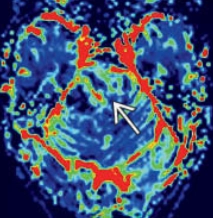

Di căn nhu mô não (Parenchymal metastases)